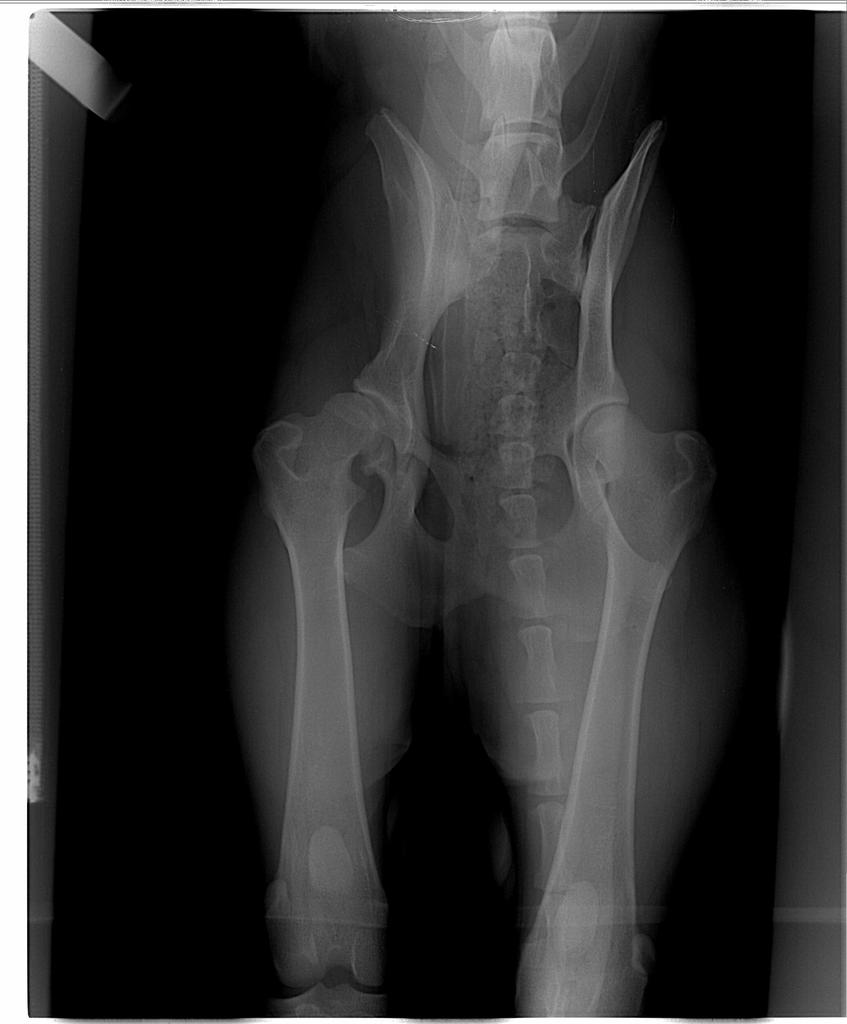

3. Podepne sie pod watek bo my niestety tez mamy dysplazje- a takie wielkie plany byly, mieszkam w UK importowalam psiaka bo brytyjska linia owczarkow niemieckich mnie nie ujela. Trenujemy do IPO, planowalismy British Seiger Show....niestety jestem przypadkiem, ktory potwierdza, ze nawet wspaniali rodzice, dziadkowie, pradziadkowie z biodrami normal, fast normal moga dac szczeniaka z dysplazja. Zbilansowane papu, suplement na stawy, bez szalenstw z psami czy skokami .....Spojrzcie tylko na rtg- zalamana jestem. Nie wiem czy udalo mi sie zalaczyc zdjecia...